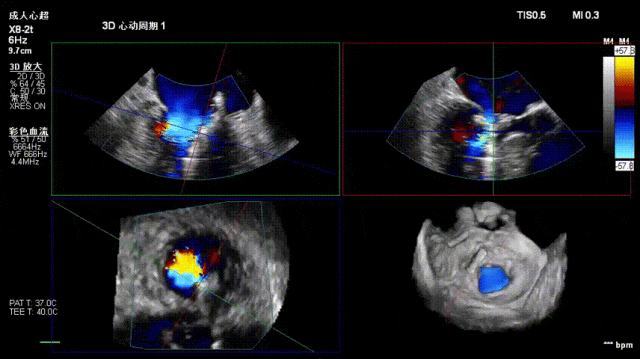

术后即刻反流降为少量,剩余瓣口面积2.57cm²,平均跨瓣压差2mmHg。

术后复查超声心动图显示:二尖瓣轻度返流,三尖瓣中度返流,二尖瓣可见金属夹回声,启闭正常;各心室大小正常,升主动脉不宽,主瓣回声增强,启闭良好;二尖瓣舒张期峰值流速1.4 m/s,功能面积2.1 cm²,跨瓣平均压差约4 mmHg。

术后心功能改善明显:LVdD 46mm,FS 33%,LA 45mm,LVDs 31mm,LVEF 62%。